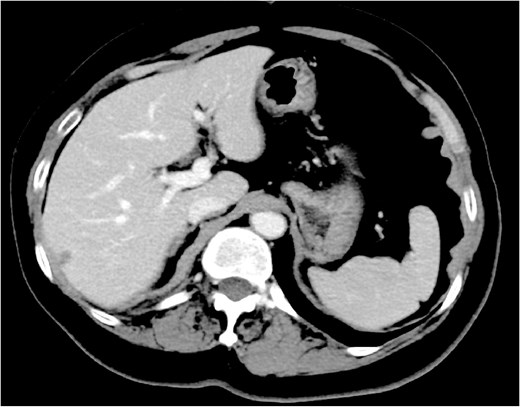

On clinical examination, a 4-cm ill-defined mass was palpated in the right breast, accompanied by a positive dimpling sign. Mammography showed an ill-defined, high-density mass in the upper-outer quadrant. Ultrasound revealed a 34-mm hypoechoic lesion with irregular margins and two swollen subclavian lymph nodes without an echogenic hilum. Dedicated breast MRI showed a 45-mm irregular, enhancing mass with early wash-in/fast wash-out kinetics (BI-RADS category 4C). Contrast-enhanced CT and positron emission tomography-CT identified a right breast mass, enlarged subclavian lymph nodes, and a solitary 2-cm splenic lesion (SUVmax 5.5) without additional distant lesions (Fig. 1A and B).

Splenic metastasis. Contrast-enhanced CT (A) and positron emission tomography-CT (B) demonstrate a solitary 2-cm splenic mass (arrows).